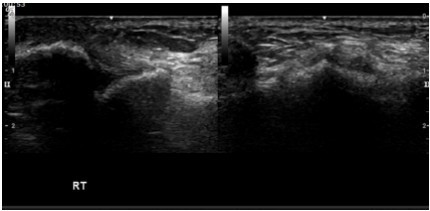

그래서 초음파 검사를 시행하였습니다. 근골격계 초음파 검사는 근육, 힘줄 그리고 인대의 손상 뿐만 아니라 혈관과 신경까지도 눈으로 확인을 할 수 있는 아주 유용한 검사 장비입니다. 이 분은 초음파검사에서 전거비인대와 삼각인대의 부분파열 소견을 보였습니다.